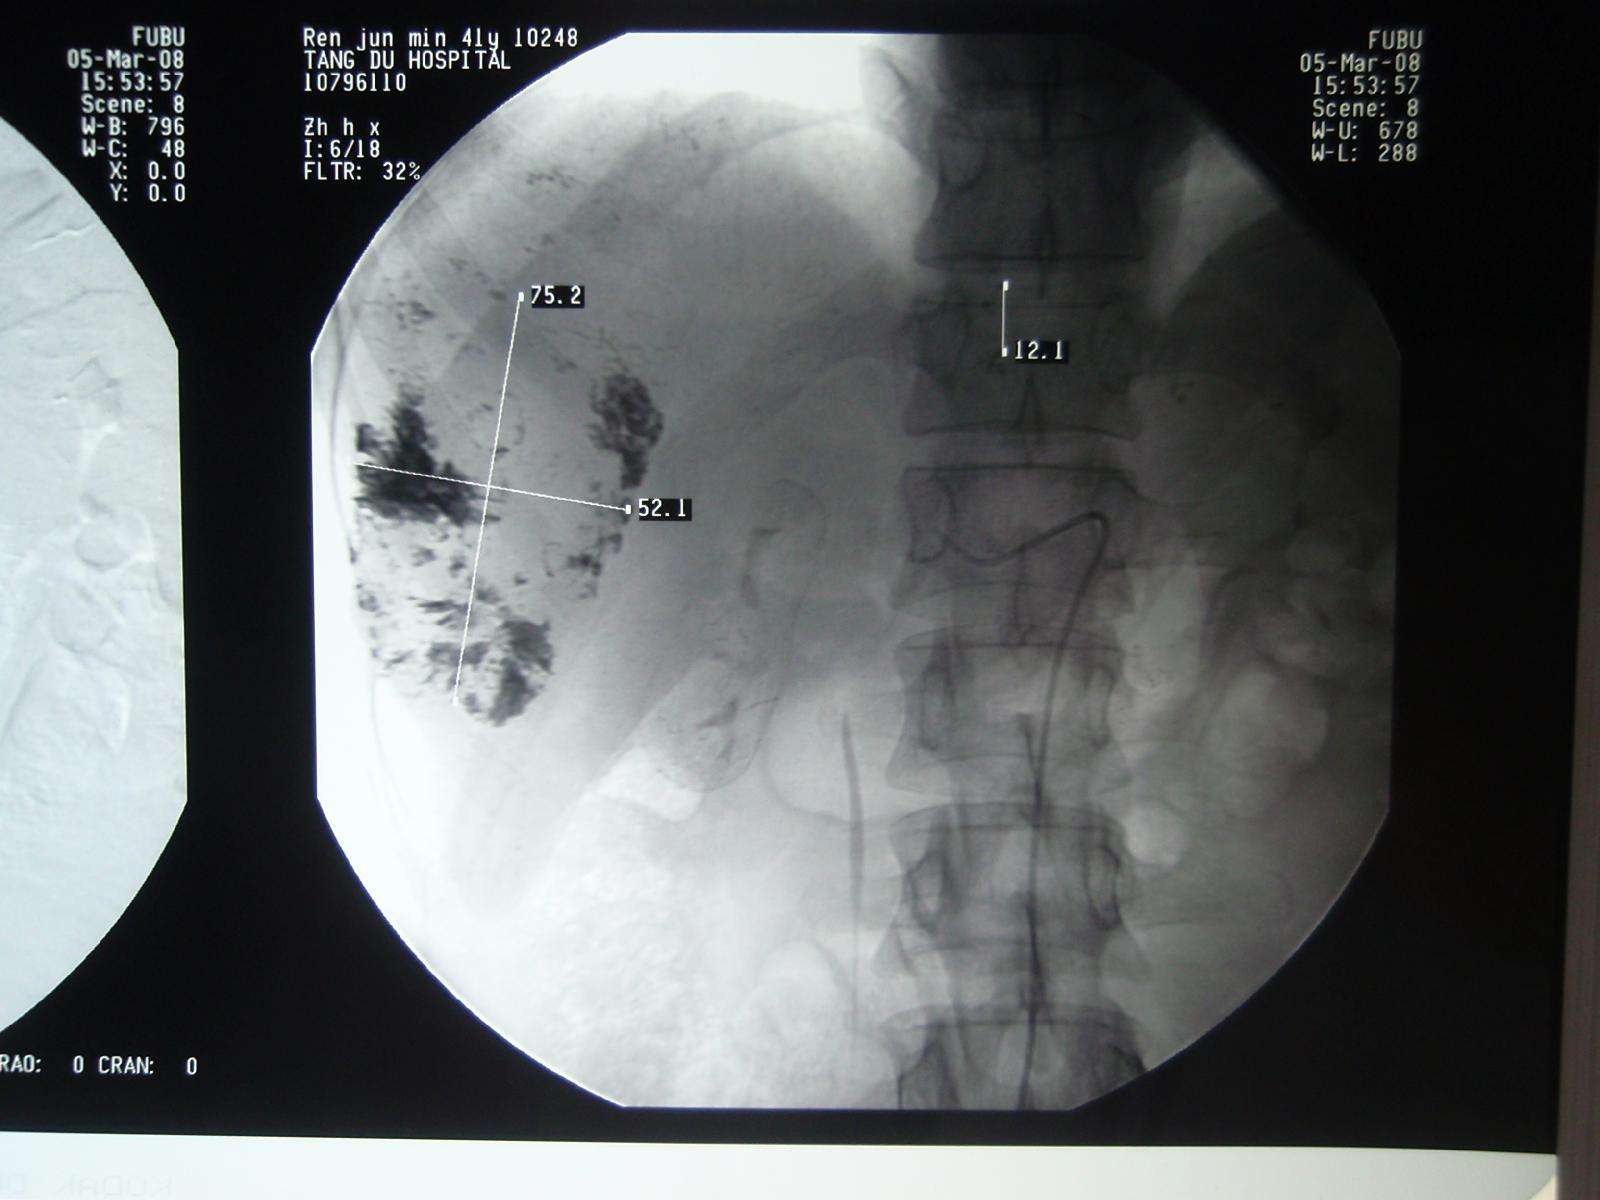

2008年3月5日张洪新教授做介入DSA造影明确诊断:

张洪新教授通过导管用碘化油栓塞瘤血管、中断病灶供血